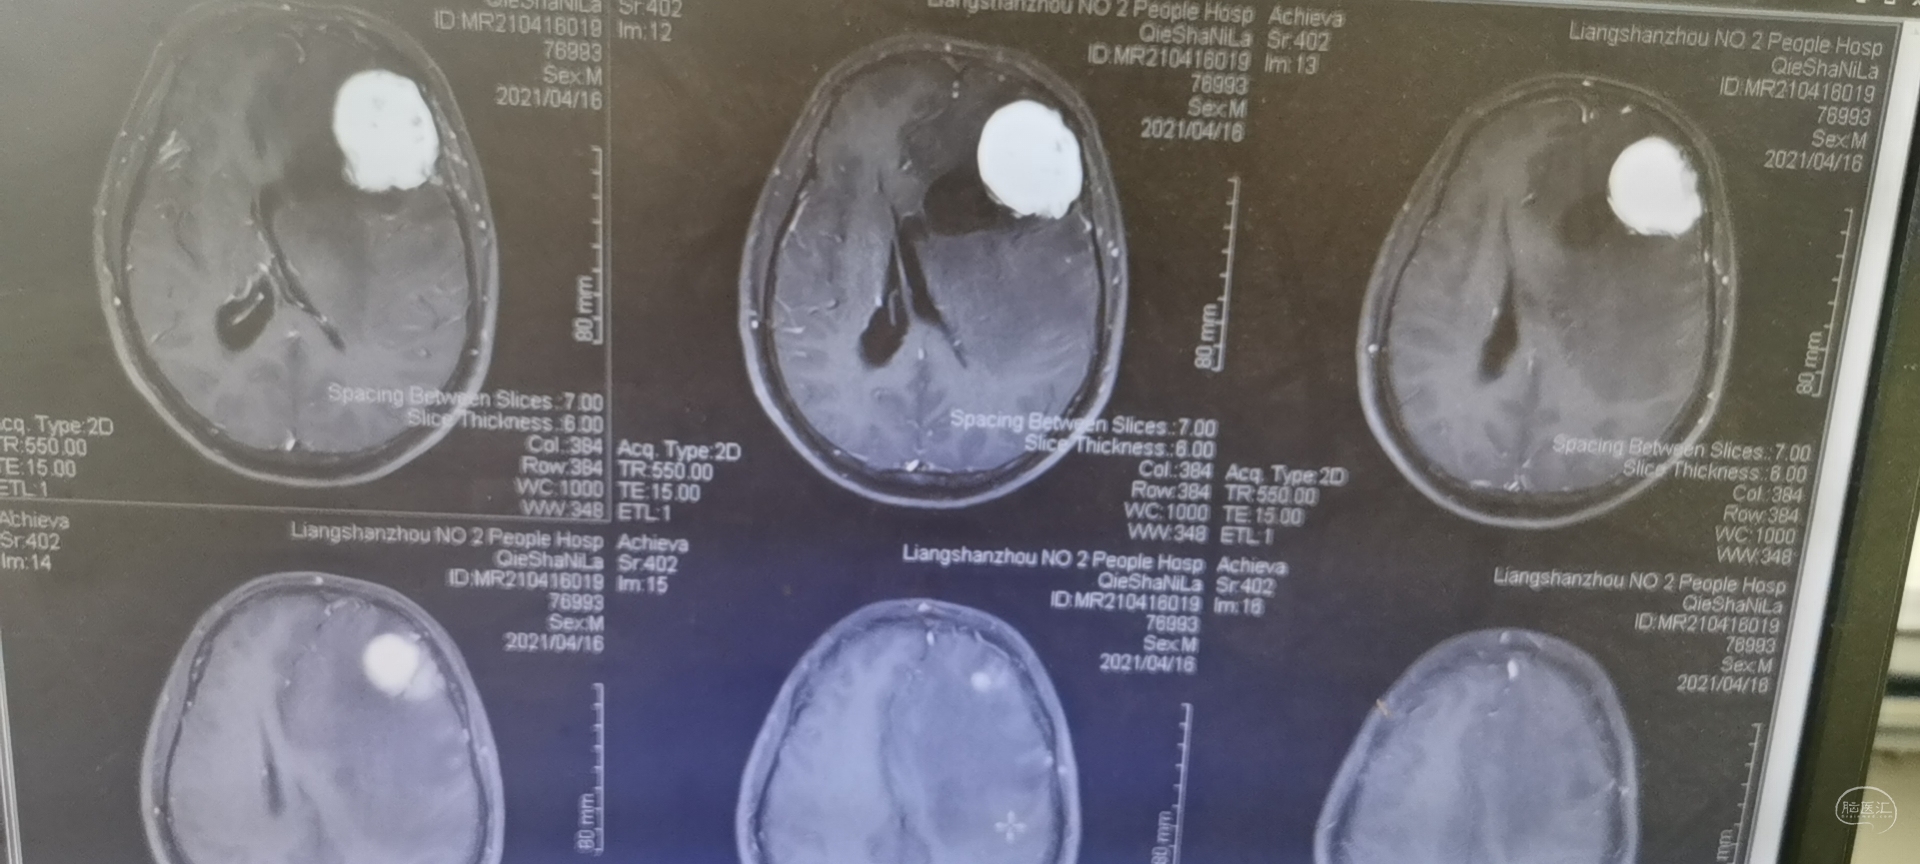

术前头颅MRI检查提示为左侧额叶占位性病变,增强强化均匀,似有脑膜征。考虑为脑膜瘤,蝶骨棘外侧型。

术后病检为胶质瘤,两结果一致,拟进一步完善免疫组化,分级分型。

术后头颅MRI检查切除满意